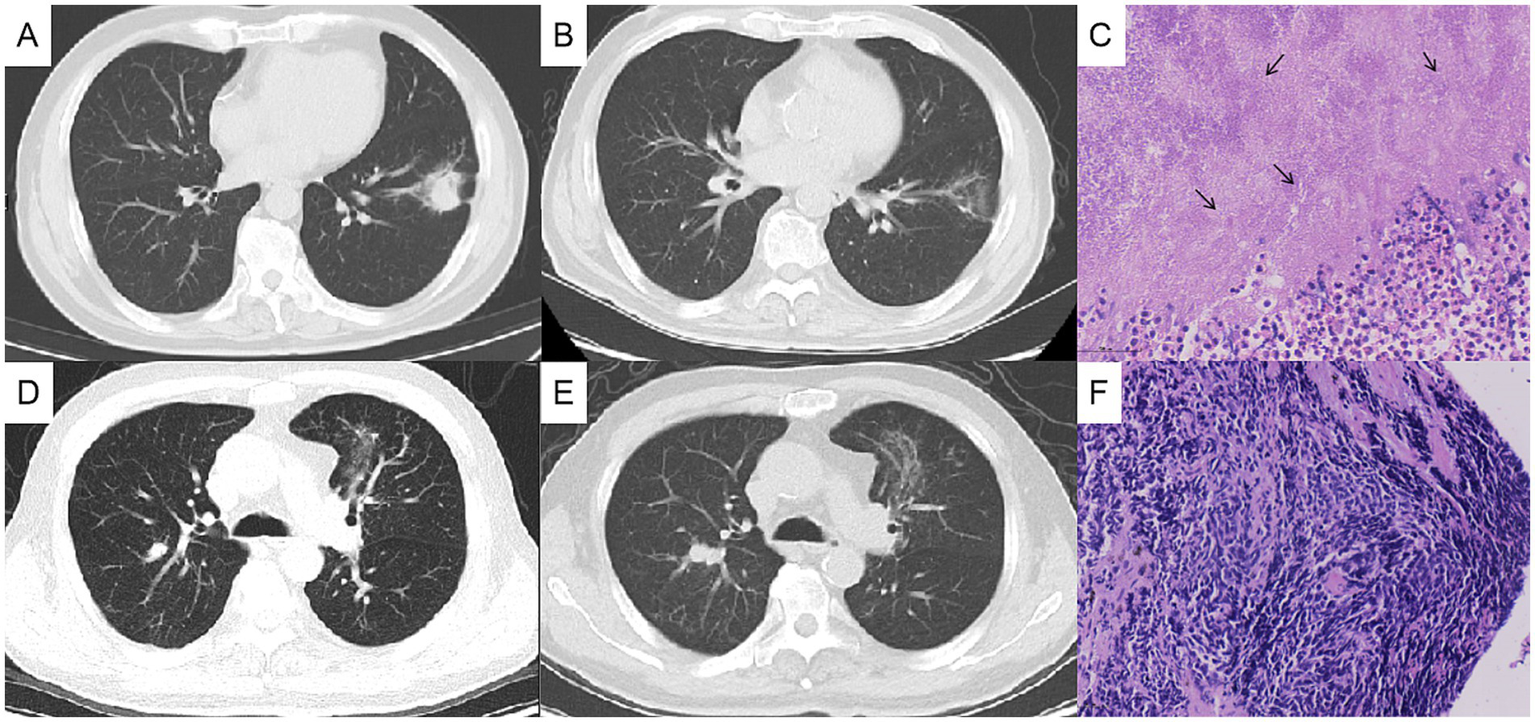

The physical examination showed no abnormality. The complete blood count, C-reactive protein (CRP), procalcitonin, erythrocyte sedimentation rate (ESR), G test, GM test, and tumor markers including CEA, SCC, CA125, pro-GRP and NSE were normal. T-SPOT was positive. Chest computed tomography (CT) depicted a 3-cm mass in the left lower lobe (Figures 1A,B) and a 1-cm nodule in the right upper lobe (Figures 1D,E). Positron emission tomography-computed tomography (PET/CT) indicated hypermetabolism in the left mass (SUVmax 5.7) (Figure 1C) and right nodule (SUVmax 4.7), both suggestive of malignancy (Figure 1F). The patient underwent a CT-guided percutaneous lung puncture biopsy of the left lower lobe mass. Pathological results revealed severe chronic active inflammation. Nodular amorphous necrotic substances were observed locally, containing thin rod-shaped thalli of varying lengths, some of which were clustered, indicative of actinomycosis (Figure 2C). Weak acid-fast staining of lung tissue was negative. Based on these findings, the patient was diagnosed with pulmonary actinomycosis. β-Lactams are recommended as first-line treatment of actinomycosis (7). Oral amoxicillin-clavulanate potassium (amoxicillin 0.2 g, clavulanate potassium 28.5 mg) were used empirically. The patient were prescribled 4 tablets orally twice daily, with a follow-up chest CT planned after 1 month. In addition, elevated blood glucose levels were detected during hospitalization, with glycosylated hemoglobin of 7.8%. He was diagnosed with type 2 diabetes, and started on hypoglycemic therapy.

Figure 1

Initial chest computed tomography (CT) and positron emission tomography/computed tomography (PET/CT) (axial). Chest CT showing a mass in the anterior and inner basal segment of the left lower lobe, about 3.1×2.5 cm, with signs of lobulation, burr, pleural adhesion and local bronchial truncation (A,B). Chest CT showed multiple small patch shadows around the bronchi of the right upper lobe and small solid nodule in the posterior segment of the right upper lobe, appropriate 1 cm in size (D,E). PET/CT indicating hypermetabolism in the nodules of the left lower lung (C) and the right upper lung (F), with SUVmax value of 5.7 and 4.7, respectively. (A, C pulmonary window, B, D mediastinal window).

Chest computed tomography (CT) changes and pathological findings. The left lung mass, measuring approximately 3 cm before treatment (A), showed significant reduction after 1 month of antibacterial therapy (B), and the histopathological analysis of the lung biopsy confirmed actinomycosis (C). The right lung nodule, initially about 1 cm in size before treatment (D), increased to approximately 2 cm after 1 month of oral antibacterial therapy (E), and the bronchoscopic biopsy pathologically confirmed the right pulmonary nodule as lung cancer (F).

After 1 month of antibacterial treatment, the patient’s cough and blood-streaked sputum were significantly reduced. A follow-up chest CT showed a marked reduction in the size of the left lung mass (Figures 2A,B). However, the right lung nodule was larger than before, with a diameter >2 cm (Figures 2D,E). He was readmitted to hospitalization for further evaluation of the right pulmonary nodule.